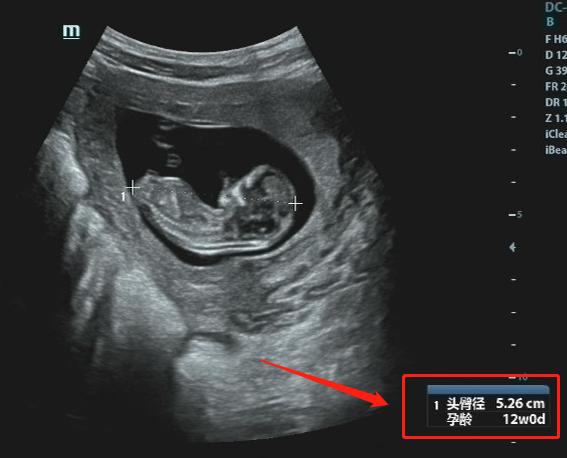

#怀孕三个月婴儿是什么样子的#

超声医师回答你:

3个月,也就是约12周。

此时胎动已经开始活跃了,只是孕妈妈可能还感受不到。但在超声下却可以看到TA很活泼哟。

当然,这个时期我们除了重点观察TA的肢体以外,此时需要重点关注NT。

NT测量一般在11-13+6周内进行。

总之,这个时期胎儿已基本成型,在12周内的孕妈妈一定要记得去正规医院产科咨询咯,因为此时需要测量NT了。